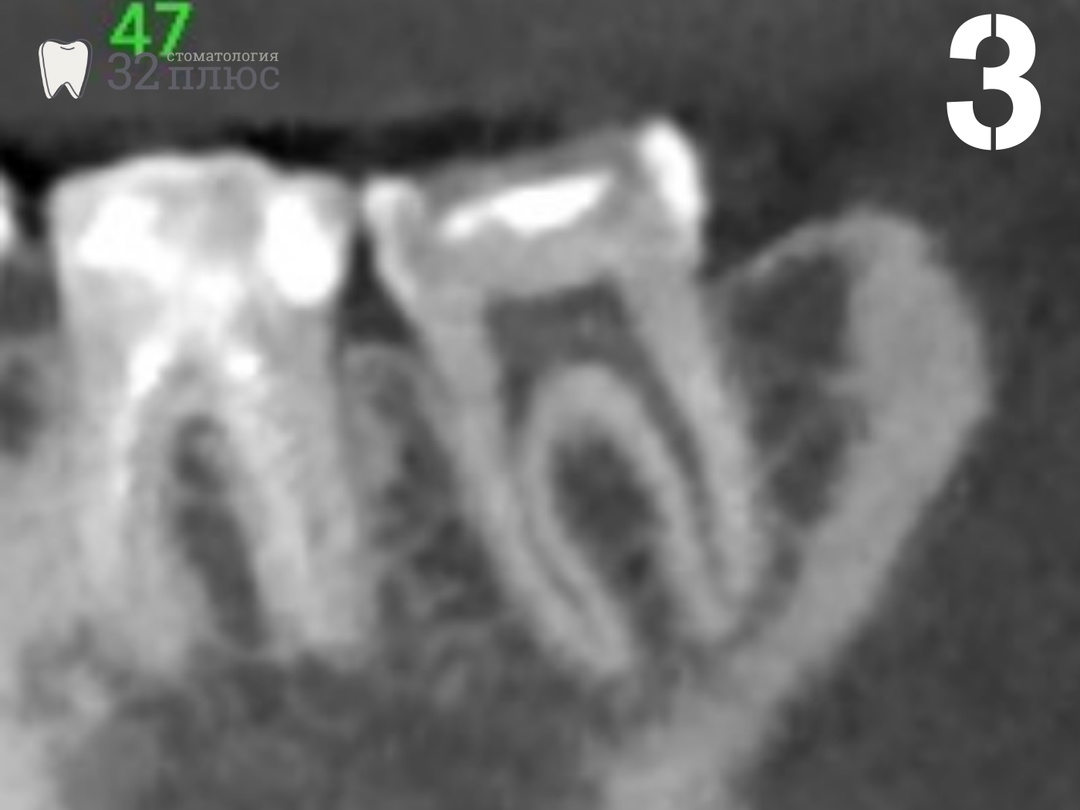

При оценке компьютерной томограммы зуба видим, что расстояние от кариозной полости до нерва достаточно большое, нерв в зубе ранее не был удалён, воспалительных изменений на корнях нет (фотография 3).